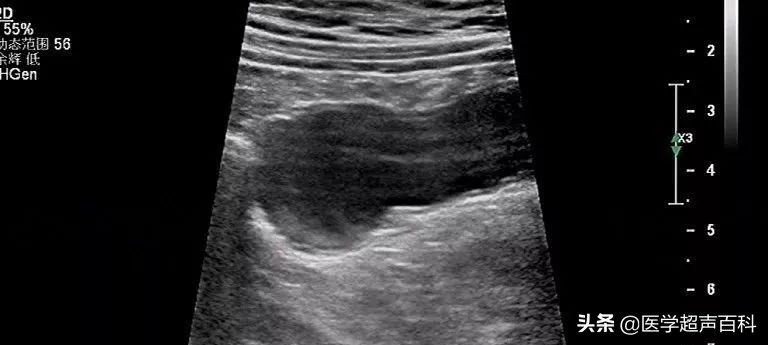

超声表现为右下腹与盲肠相连的类圆形或管状无回声包块,其横径通常大于1.5cm,包块边界清楚,壁厚,内壁不光整,内部可呈无回声或条带状高回声分隔混杂的不均质表现(可误认为是囊实混合性包块),也有病例报道较大的肿瘤可呈“洋葱皮”样,CDFI:部分肿瘤囊壁内可见少量血流信号。